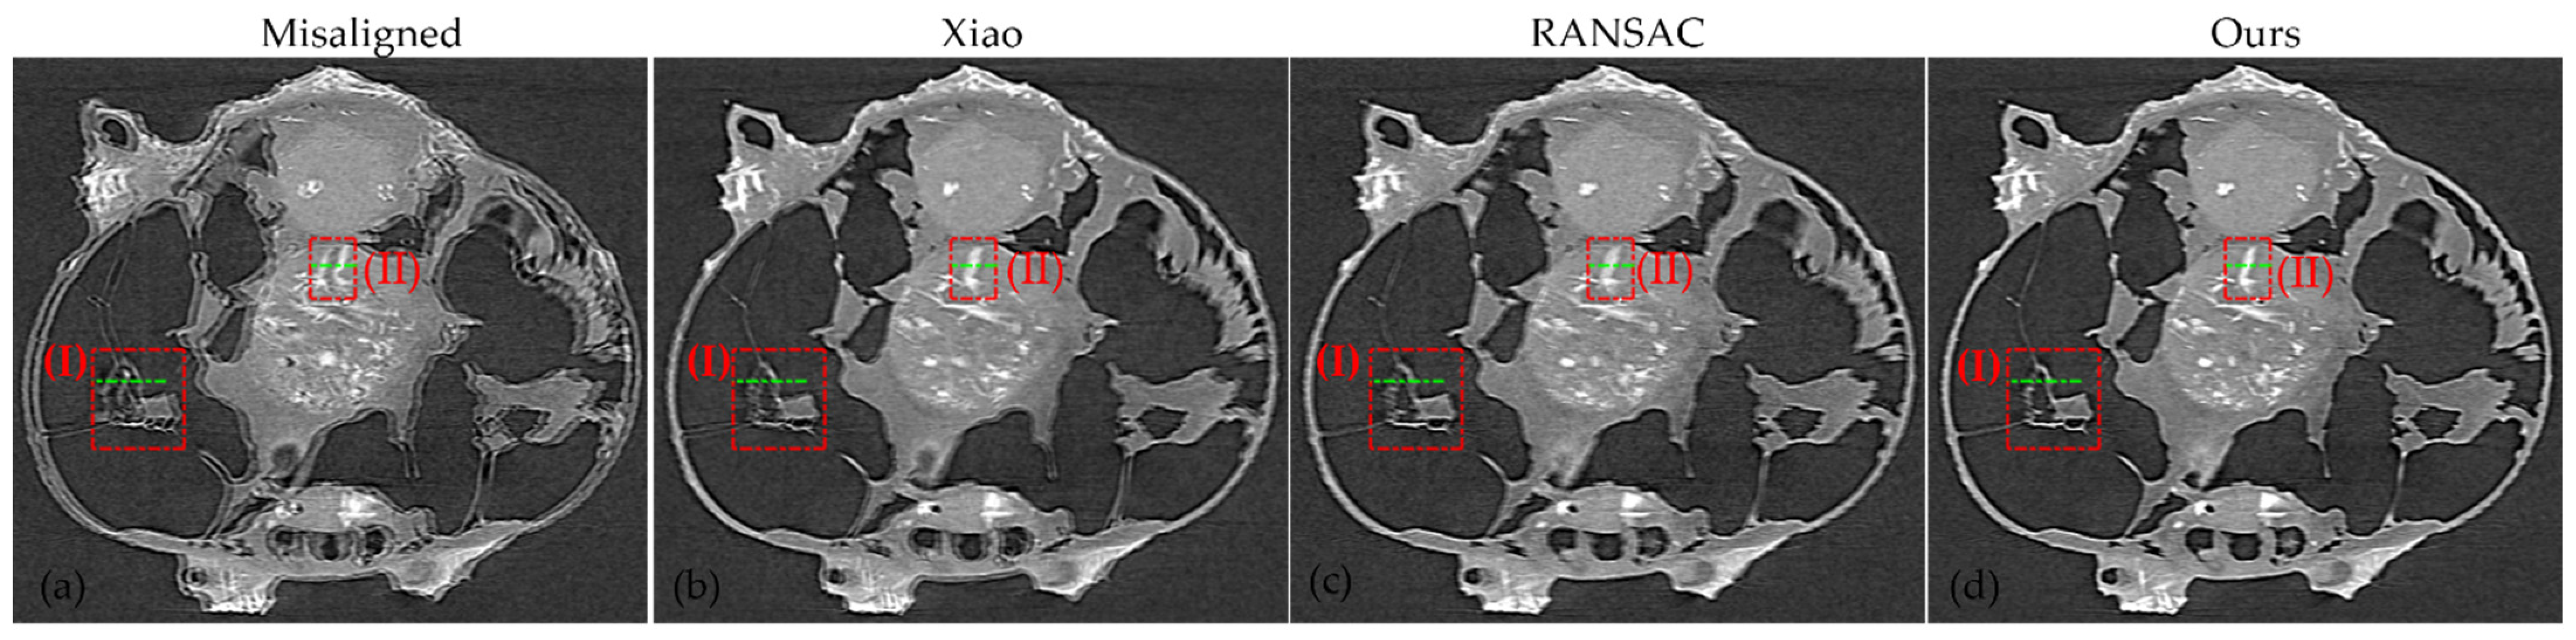

3.2. Nanotomography Experimental Section